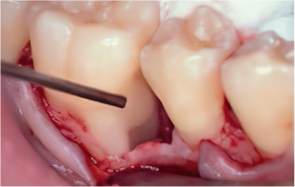

-

STEP 03

Removal of calculus and plaque

STEP 04

Emdogain application